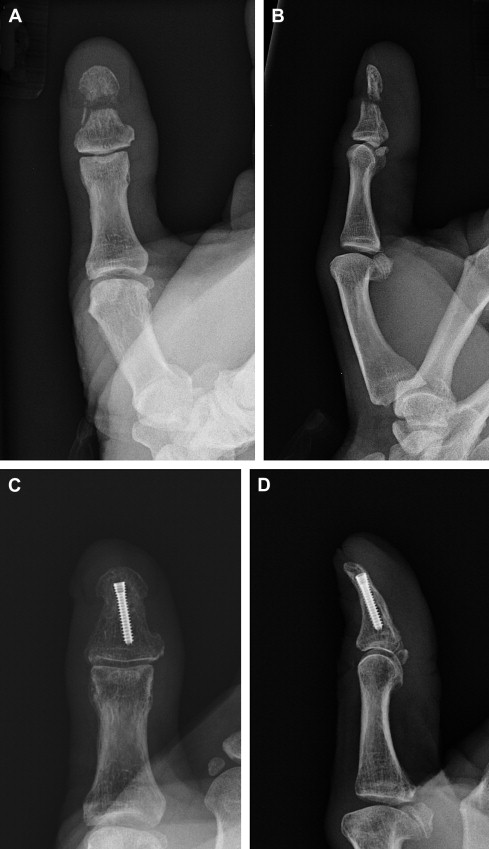

Arthrodesis is useful for articular nonunions associated with joint stiffness. This digit is likely to remain stiff following healing of the nonunion, and arthrodesis allows for internal fixation to cross the joint, allowing for a longer implant and more stability. Both the joint and nonunion site should be debrided, bone grafted, and stabilized ( Fig. 1 ).

When the nonunion is in the shaft of the distal phalanx, this can often be treated with compression across the nonunion site, either through an open approach or with percutaneous compression screw placement ( Fig. 2 ).